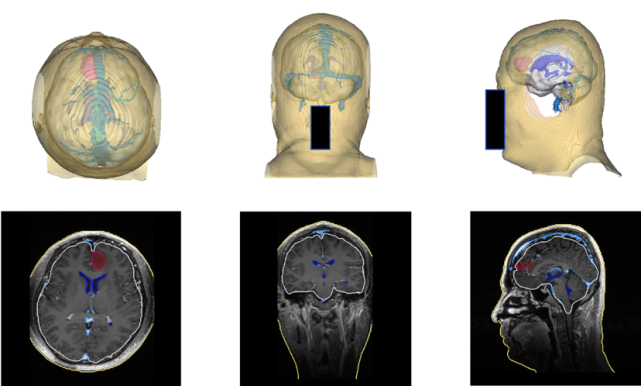

具体来看,国产手术导航系统能在术前、术中等多个环节,辅助医生提升诊疗效率。术前,基于AI和影像技术,该手术导航系统能够将磁共振、CT等影像自动进行分割重建及三维可视化处理,通过腾讯AI Lab的算法能力,一键生成定制化的3D“透明脑”,方便医生制定手术计划,向病人和家属讲解手术方案。

图片

(术前“透明脑”生成)